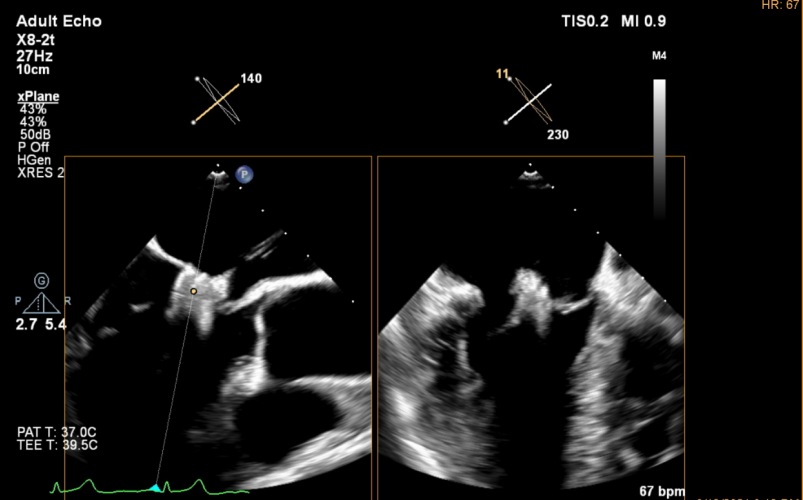

本次手术由尚小珂、陈澍,钟禹成教授为术者,超声医学科谢明星教授全程TEE监控引导下完成,法国波尔多里尔大学Thomas Modine教授远程指导。术后即刻超声心动图评估返流降至轻度,夹合器锚定良好、输送系统顺利撤出体外,手术取得圆满成功。

术后即刻超声心动图下夹合器形态